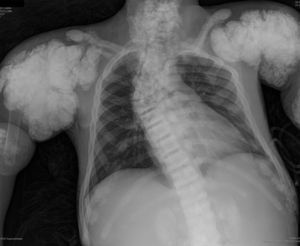

En la radiografía de tórax (fig. 1) se observaron calcificaciones periarticulares en los hombros de aspecto nodular, osteoesclerosis vertebral y colapsos vertebrales dorsales 5 y 6, secuelas de fracturas costales y fractura del húmero derecho. En la radiografía de abdomen (fig. 2) se apreciaron nefrocalcinosis bilateral, osteoesclerosis vertebral y en huesos de la pelvis, calcificaciones periarticulares de aspecto nodular y fractura subtrocantérica bilateral.

Calcificaciones periarticulares de aspecto nodular en hombros. Osteoesclerosis platillovertebrales superior e inferior (columna en jersey de rugby) y colapsos vertebrales dorsales 5 y 6. Crecimiento en forma de bulbo de los extremos de las costillas y clavículas. Osteoesclerosis de clavículas y secuelas de fracturas costales. Fractura del húmero derecho.